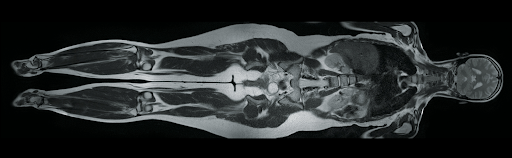

Поддержка различных протоколов сканирования, включая сканирование всего тела

Atlas Integrated Matrix (AIM) обеспечивает улучшенное сигнально-шумовое соотношение и точность изображений. Позволяет получать более детализированные изображения в реальном времени. Применяется для диагностики в различных областях медицины, включая кардиологию, неврологию, онкологию и другие.